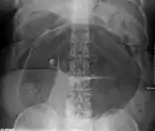

An x-ray of a person with a small bowel volvulus.

- Abdominal x-ray – tire-like shadow arising from right iliac fossa and passing to left